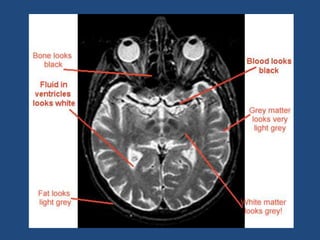

Relaxation Process 1-NMV recoversand realign to B0 this process called "T1 Recovery" 2-Nuclei loose Precessional coherence or dephase and NMV decay in the transverse plane this process called "T2 Decay"

T1 time &T2 Decay are an intrinsic contrast parameter that are inherent to tissue being imaged. T1WI